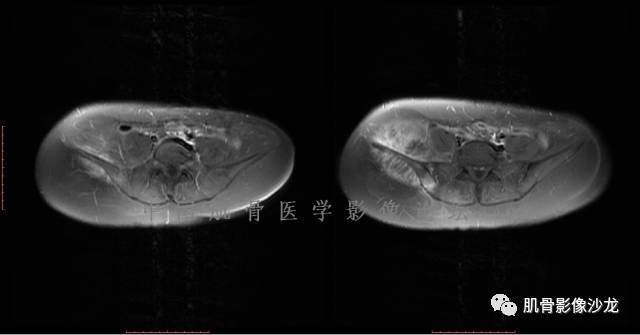

患者于2月前无明显诱因下出现腰骶部疼痛,夜间为重,逐渐加重伴左下肢麻木、疼痛,并有行走活动受限,在我院就诊,摄腰椎及骶髂部CT提示:腰椎骨质退变,腰3-4、4-5椎间盘膨出,骶髂关节炎。自用非甾体抗炎药无好转,再次来院就诊,门诊拟“骶髂关节炎”收住我科。病程无间歇性跛行,大小便正常。

专科检查:神清,脊柱无侧弯后凸畸形,椎体各节段无压、叩痛,双侧棘突旁无压痛,双侧骶髂关节压痛明显,左下肢放射痛,浅感觉较健侧减退,腰椎前屈后伸活动受限,膝、跟腱反射正常。

辅助检查:腰椎及骶髂部CT提示:腰椎骨质退变,腰3-4、4-5椎间盘膨出,骶髂关节炎。

雪舞 :第二例,位于骶骨,有骨质破坏并有软组织肿块,软组织肿块边界清

雪舞 :第二例挺难的,骨质破坏是溶骨性的,局部皮质中断,软组织肿块外缘光滑